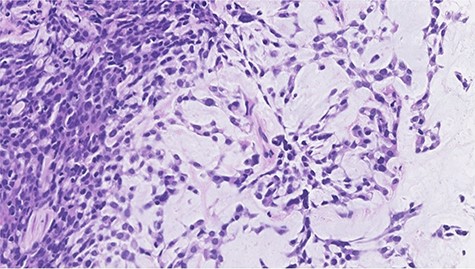

Histopathological features of right breast tumor. The biopsy specimen showed high-grade carcinoma cells arranged in solid sheet or thin trabecular structures directly producing matrix, suspected to be matrix-producing carcinoma (metaplastic carcinoma) (hematoxylin and eosin stain, ×400).

Histopathological features of left breast tumor. The biopsy specimen demonstrated invasive carcinoma with features of metaplastic carcinoma, i.e. without ductal structure, with tumor cell matrix-producing or some spindle cell characteristics (hematoxylin and eosin stain, ×400).